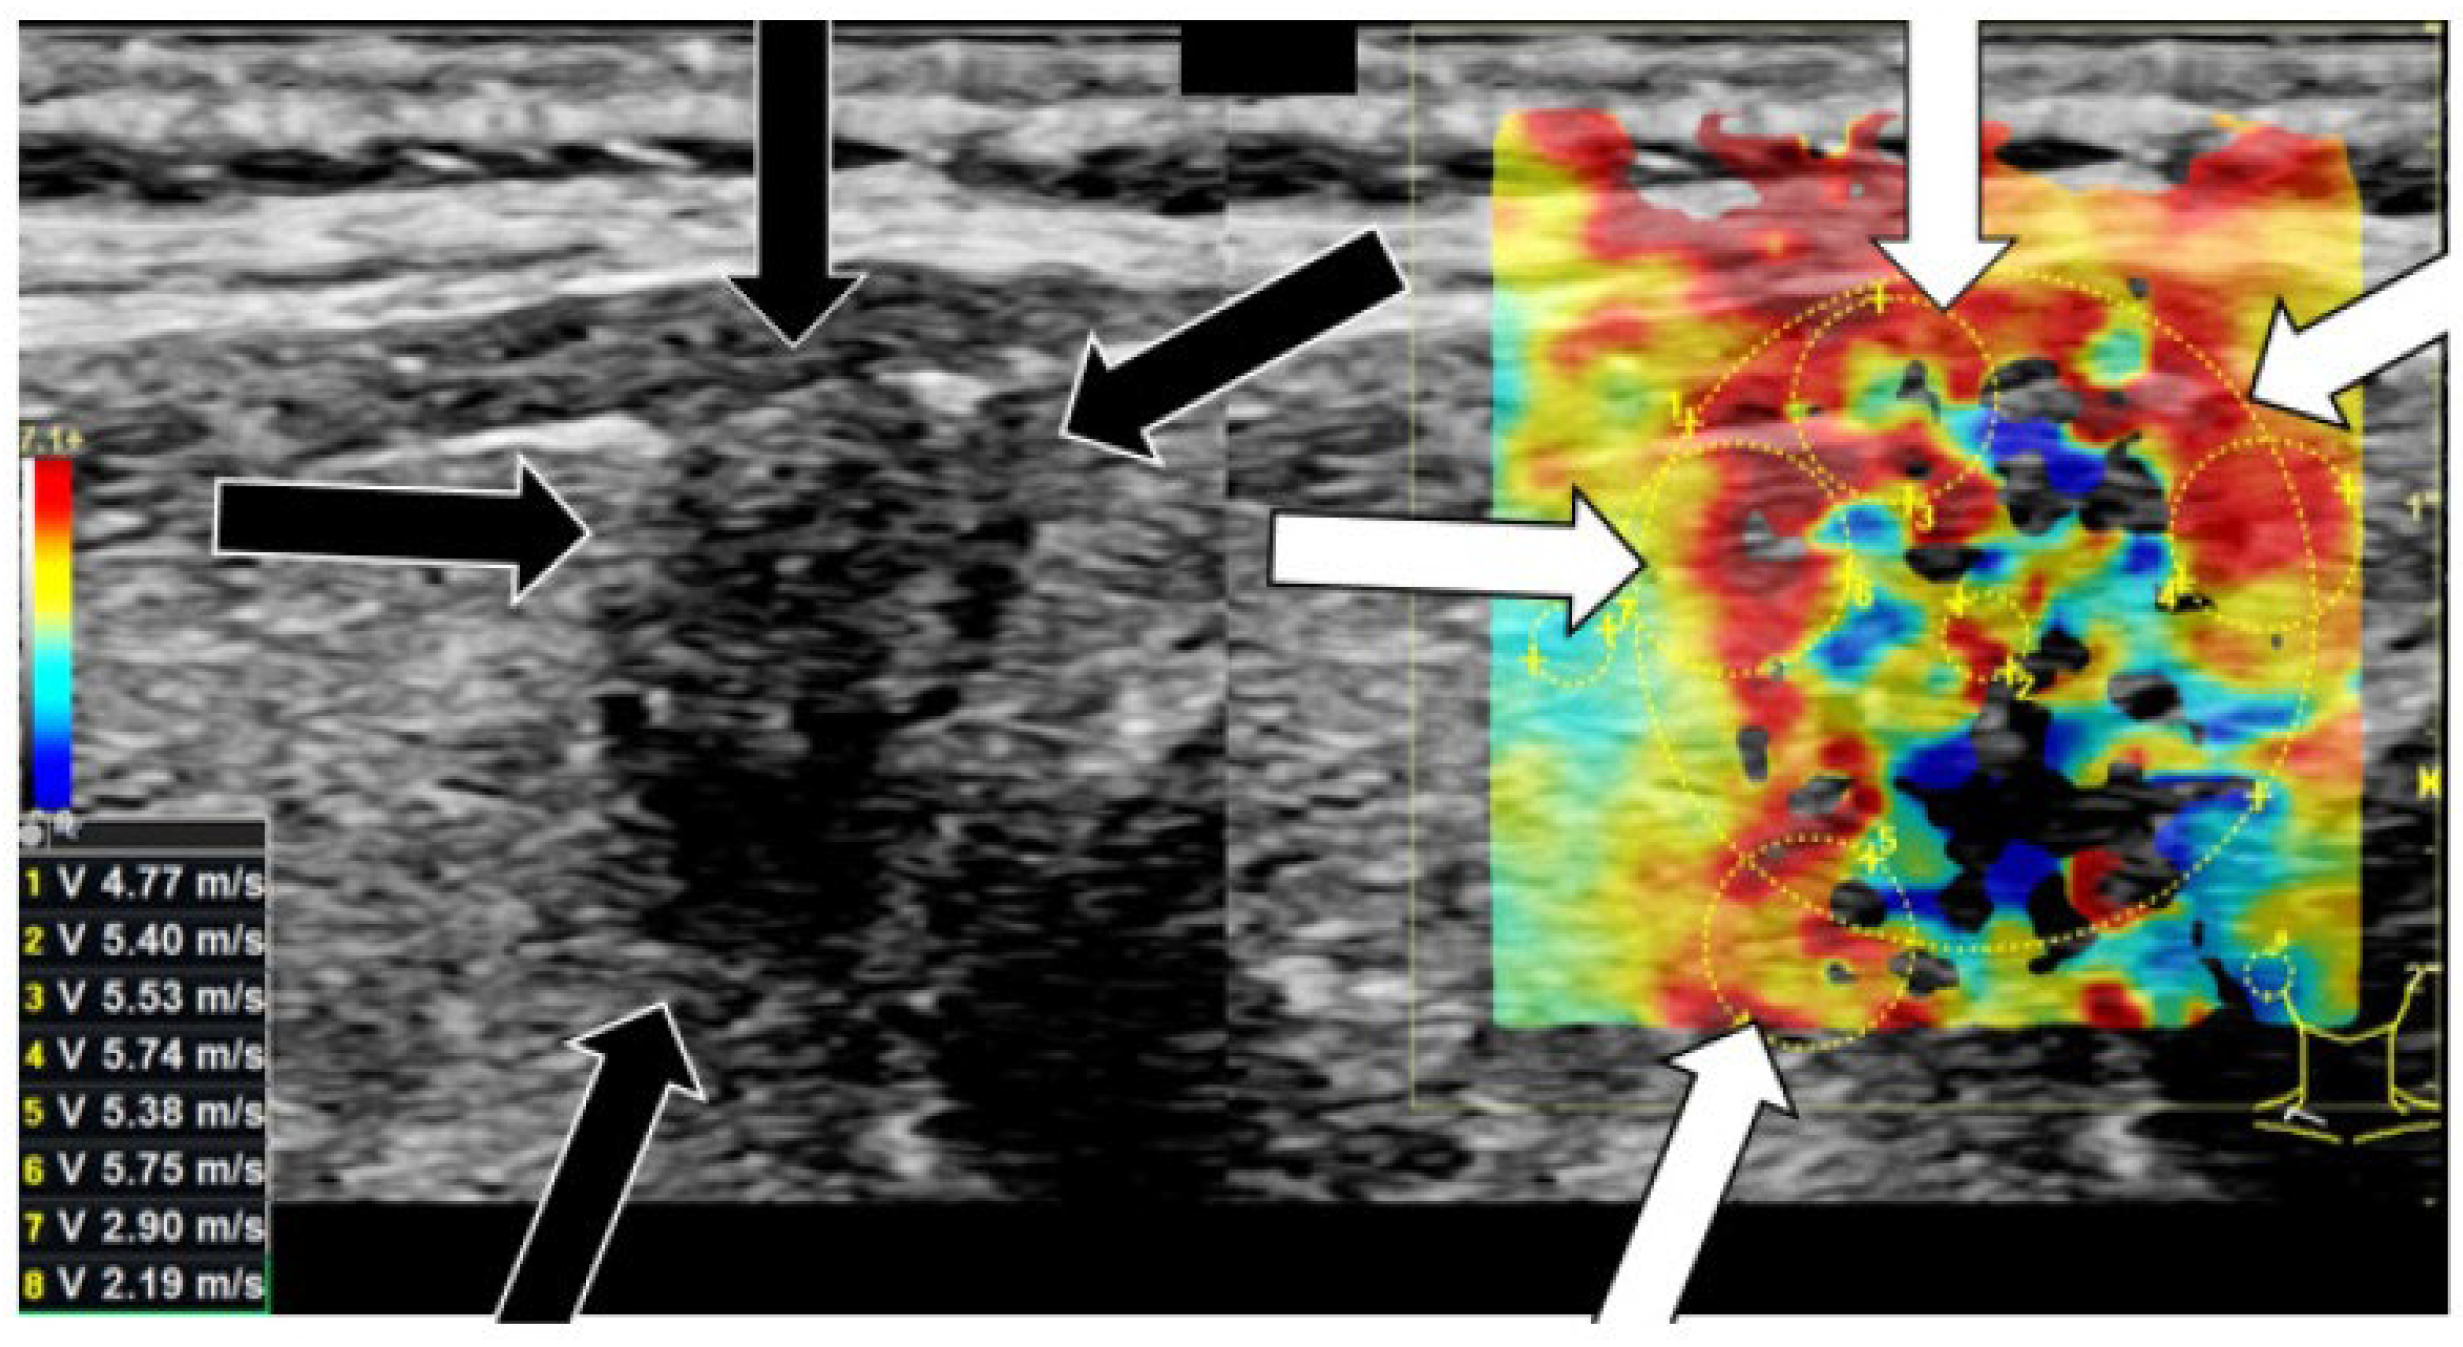

- Brandenstein, M.; Wiesinger, I.; Künzel, J.; Hornung, M.; Stroszczynski, C.; Jung, E.-M. Multiparametric sonographic imaging of thyroid lesions: Chances of B-mode, elastography and CEUS in relation to preoperative histopathology. Cancers 2022, 14, 4745. [Google Scholar] [CrossRef]